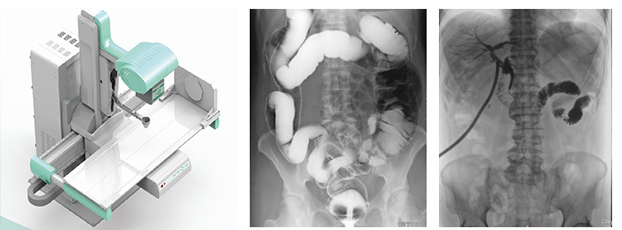

動態DR是一款多功能DR,能夠數字拍片、數字透視、數字造影。

動態DR是使用多功能動態數字化探測器成像的直接數字化X射線攝影系統。

動態DR具有大幅面(17inch×17inch)高清拍片、大幅面(17inch×17inch)透視、視頻實時保存回放、可視化造影、毫秒級點片等基礎功能,以及斷層融合、數字減影等延展性功能。

普愛醫療作為全球較好的數字影像設備供應商,專注于DR系列產品的技術創新,在全國范圍內率先推出動態DR。以其“一機多用”集常規拍片、胃腸、透視、造影于一體的多功能作用深受放射科臨床醫生的鐘意。

普愛醫療的動態DR擁有滿足各類臨床應用的多種功能、高品質的影像后處理系統,動態CCD探測器的核心技術更方便實現技術升級,對醫院提高診療水平和診療效率、降低設備重復購買成本具有重要作用,是功能強大、性能優異的一款高端數字設備。如果您想購買普愛醫療的動態DR,或想了解產品具體技術參數,歡迎聯系我們。